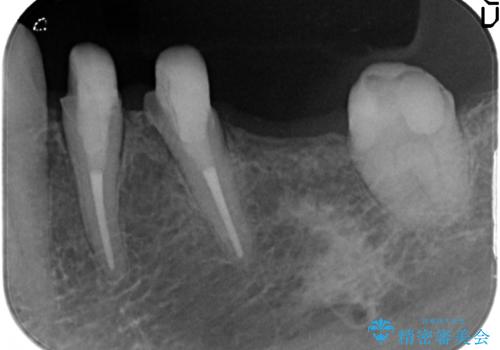

- 古くなり黒ずんできたブリッジのやりかえを希望され来院されました。

老朽化した銀パラジウム合金のブリッジを除去し、ジルコニア製のブリッジでやりかえを計画します。